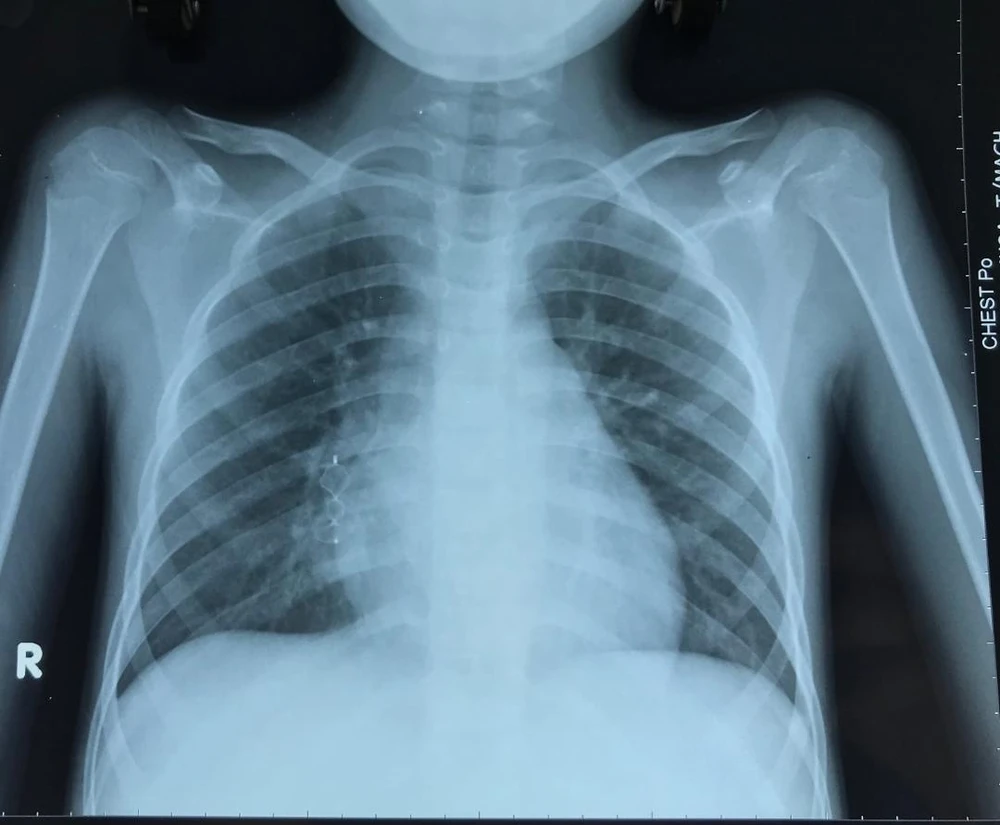

X-quang sau can thiệp của bé trai. Ảnh: BVCC

Vì túi phình lớn có nguy cơ vỡ gây xuất huyết phổi nên BS CKII Nguyễn Minh Trí Việt, Trưởng khoa Tim mạch, đã tiến hành thông tim can thiệp đóng túi phình bằng dụng cụ. Sau can thiệp, bé trai đã ổn định và được xuất viện, tái khám và kiểm tra định kỳ tại khoa Tim mạch.